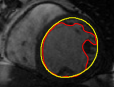

The problem above is a generalization of Horn & Schunck optical flow. Note that solving for the Horn & Schunck optical flow within each region separately does not lead to motions such that at the interface, they have equal normal components (see Figure 1), whereas the solution of (5) to be presented in subsequent sections does. Note that computing Horn & Schunck optical flow in each region requires boundary conditions (and typically they are chosen to be Neumann boundary conditions: and on ). Note that replacing these boundary conditions with the boundary constraint (6) does not specify a unique solution. Also, while Horn & Schunck optical flow computed on the whole domain naturally gives a globally smooth motion, which by default satisfies matching normals at the interface, this is not natural for the ventricles / myocardium, where different motions exist in the regions (see Figure 2), and the motions should not be smoothed across the regions.

![]() |

| image + boundary | global optical flow | our method | our method (motion decomp.) |